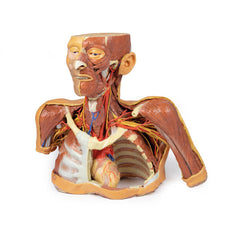

3D Printed Thoracic Cross Section at T6

This model is a cross-section of the thorax at the level of the T6 vertebra. Beginning posteromedially at the spinal

cord within the vertebral canal, then moving radially, the costovertebral joints of the 6th ribs are visible,

followed by several other ribs around the margin of the thoracic cavity, a pair of which unite anteriorly with the

sternum via the costosternal joints. Additionally, the oesophagus and descending aorta are visible anterior and

lateral to the T6 vertebral body, respectively.

Inside the plural space, lined by the parietal pleura,

reside the

inferior and middle lobes of the right lung and the inferior lobe of the left lung.

In the middle

mediastinum the

heart, within the pericardium, is transacted to reveal the left atrium posteriorly, then moving clockwise, the

aortic valve, right ventricle and the right atrium.